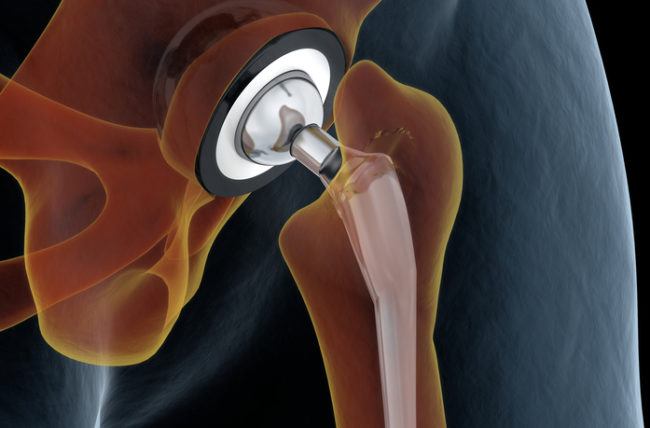

Joints Replacement

Hip Replacement Surgery